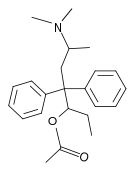

Methadols

Structures

| Other open chain opioids | ||||

|---|---|---|---|---|

|

|

|

Noracetylmethadol | |